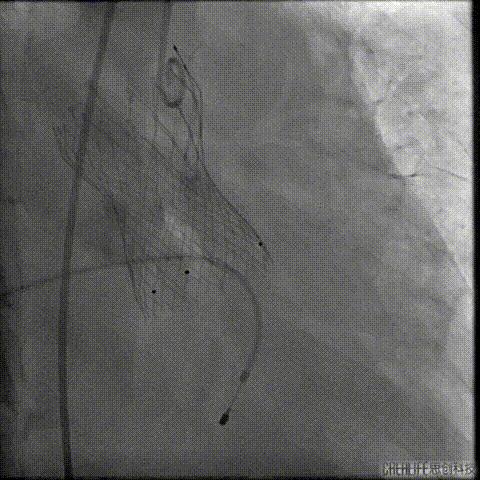

预扩主动脉瓣

NUMED 25mm*40球囊

180/分起搏下预扩主动脉瓣

左冠血流受到影响

予ECOM支持

扩瓣结束后,患者出现心跳骤停

予胸外按压,并予ECOM支持后

患者恢复自主心率